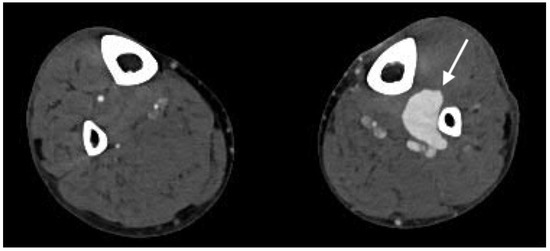

2.4.6. Arteriovenous Fistula